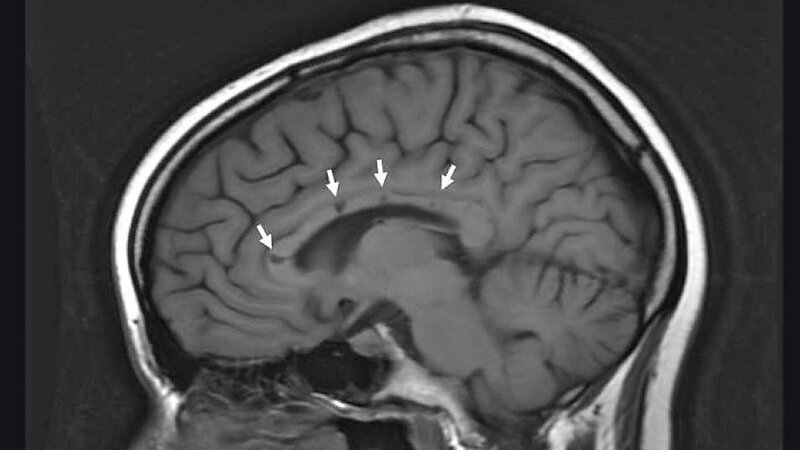

Beim Susac-Syndrom handelt es sich um eine seltene, entzündliche Erkrankung, die wahrscheinlich autoimmun vermittelt ist. Innerhalb weniger Tage kommt es zu Sehstörungen, Schwerhörigkeit und neurologischen Symptomen.

Susac syndrome is a rare inflammatory disease, which is probably caused by an autoimmune disorder. Visual disturbances, hearing loss and neurological symptoms occur within a few days.